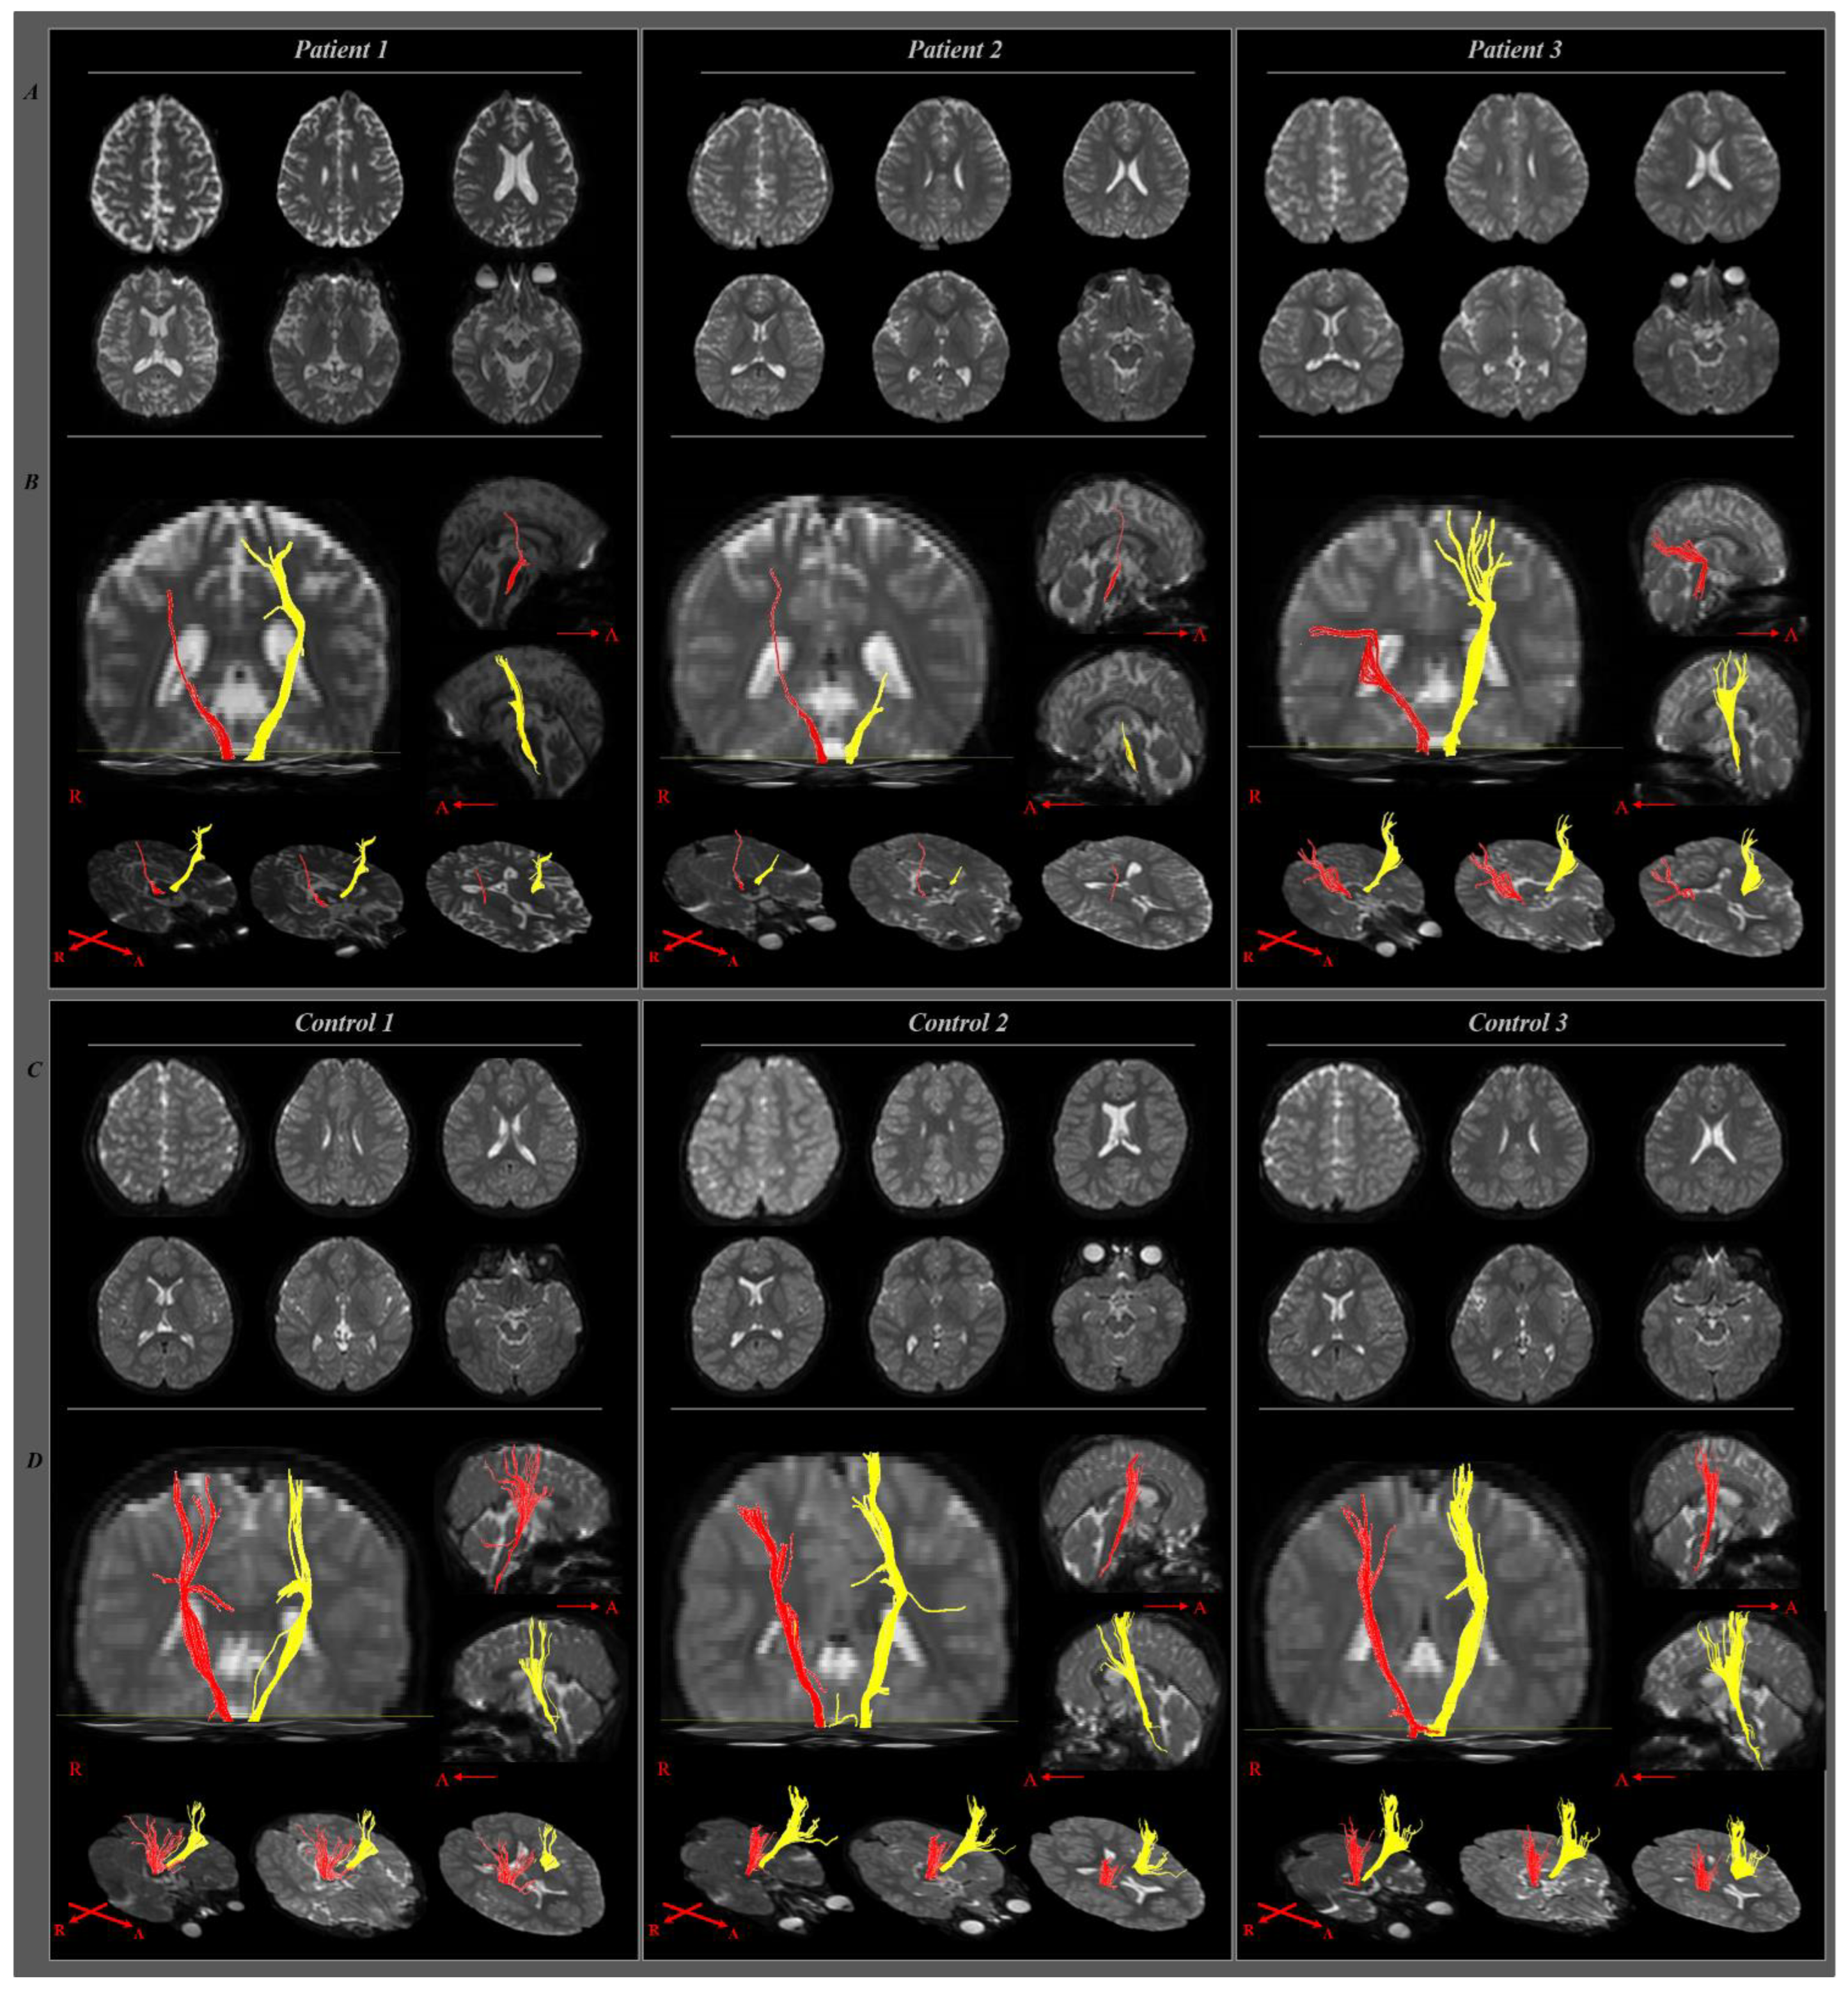

2. Case Presentation

2.1. Case 1

2.2. Case 2

2.3. Case 3

3. Discussion